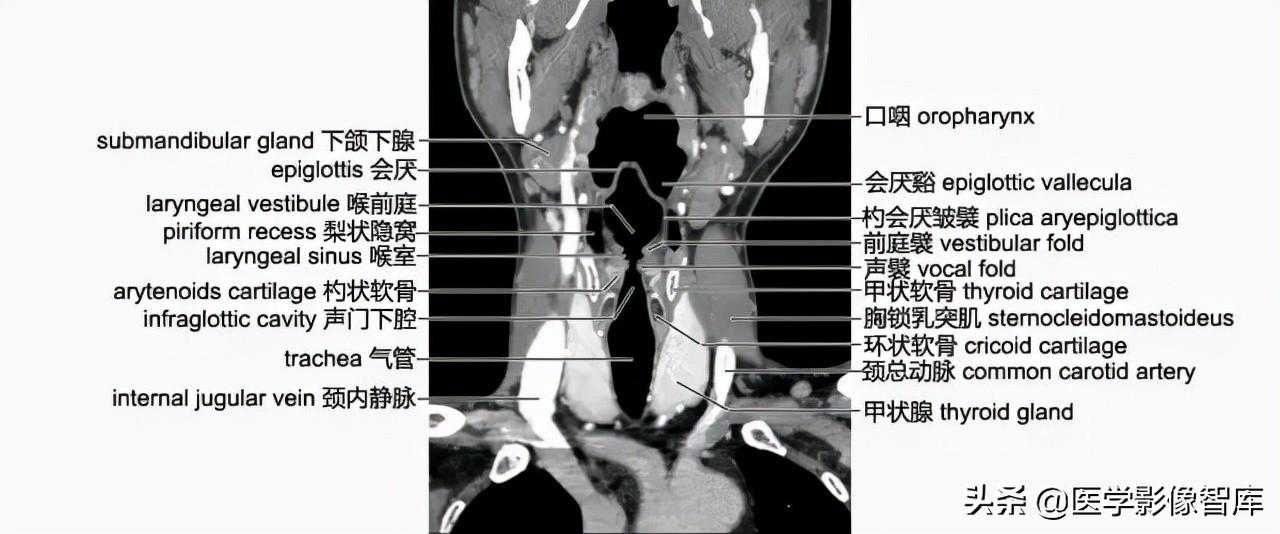

冠状面解剖

在垂直于喉室中部的冠状面像上,会厌软骨在黑色的气腔内,呈“八”字拱形突入口咽,其下是喉咽。会厌软骨外侧与口咽侧壁间的腔隙即为会厌谿。与会厌软骨下部相连的条形软组织影是杓会厌皱襞,皱襞外与喉咽壁间的三角形腔隙称梨状隐窝。隐窝外下壁的斜形高密度影是甲状软骨板。杓会厌皱襞下部可见向腔内突出的前庭襞(室带的组成部分),其下方的另一个突起,是声襞,两个突起之间的梭形隐窝就是喉室,为喉中间腔向两侧的延伸。前庭襞、杓会厌皱襞和会厌软骨所围成的腔隙是喉前庭。在声门下腔与气管壁的外侧分别可见环状软骨、甲状腺、颈总动脉、颈内静脉和胸锁乳突肌等结构(图4-3-9)。

图4-3-9颈部冠状层面(CT重建图像)